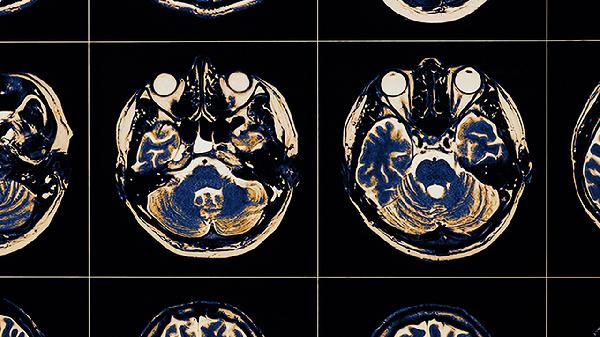

初期脑血栓需注意控制基础疾病、规范用药、调整生活方式及监测症状变化。脑血栓是脑动脉因血栓形成导致血流中断的疾病,早期干预有助于改善预后。